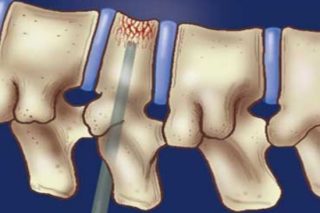

Вертебропластика или точнее чрезкожная вертебропластика выполняется под местной анестезией с использованием любого местного анестетика (новокаин, лидокаин и т.д.). Благодаря местной анестезии хирург может контролировать ощущения пациента, что позволяет свести до минимума риск повреждения нервных структур во время операции. Вертебропластика обязательно выполняется с использованием постоянного рентген-контроля с помощью ЭОПа (электронно-оптического преобразователя) или С-дуги, что одно и то же. Специальная игла после обезболивания проводится через кожу, мышцы и ножку дужки позвонка в тело позвонка с той стороны, где находится гемангиома. Затем через иглу вводится в тело позвонка с гемангиомой специальный костный цемент, который быстро застывает. Гемангиома разрушается, заполняется цементом и перестает расти, а тело позвонка укрепляется.

- Установка винтовой транспедикулярной титановой системы с продольными балками по показаниям.